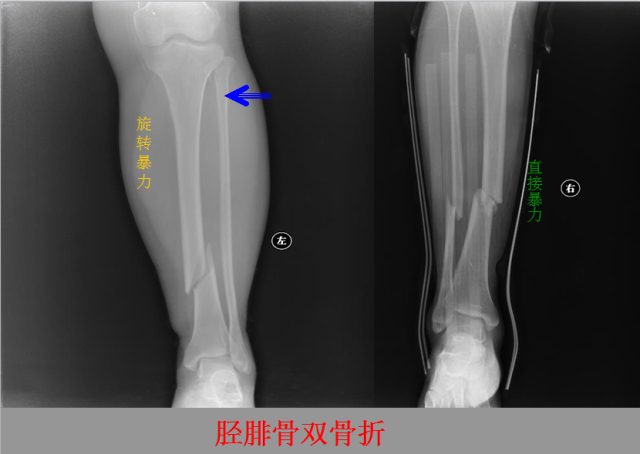

骨折篇

定义:骨折{Fracture}是指骨的完整性和连续性的折裂或粉碎。包括创伤性骨折、疲劳性骨折和病例理性骨折。 临床上以创伤性骨折*常见。